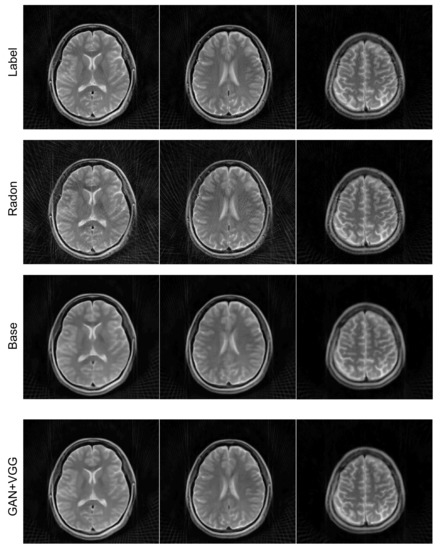

4.3. Loss Functions

To further optimize the proposed network for image reconstruction, two different losses were additionally calculated along with the baseline loss function of the Euclidean distance: adversarial loss and perceptual loss. The effects of the loss functions were analyzed for the undersampled k-space data with R = 4. The ETER-net with different loss functions was also compared with two different image-domain to image-domain reconstruction methods, DFU [27] and DAGAN [19], and a k-domain to k-domain reconstruction method, k-space deep learning for accelerated MRI [16]. Figure 7 shows the result images and errors, and Figure 8 shows the quantitative analysis of the reconstructed images. Figure 7b,c show a substantial amount of image artifacts and aliasing patterns, owing to the regular subsampling of the input k-space data. In contrast, the proposed methods show quality results, and the aliasing artifacts are eliminated in these images (columns (e–h)). By comparing the images reconstructed with various loss functions, it can be concluded that the loss functions, including the Euclidean distance, adversarial loss, and perceptual loss, provided the best performance in terms of image quality.

Figure 7.

Comparison of previous methods with the proposed method. first and third row: Magnitude images. second and fourth row: Corresponding error maps in the 1/10 range. (a): Ground truth magnitude images (label images). The images are reconstructed by (b): DFU, (c): DAGAN, (d): k-space deep learning, (e): baseline loss, (f): baseline loss + perceptual loss, (g): baseline loss + adversarial loss, and (h): baseline loss + adversarial loss + perceptual loss.